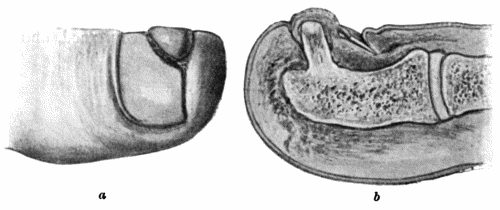

Another modification is to raise the flap but leave it connected at both ends like the piers of a bridge; this method is well suited to defects of skin on the dorsum of the fingers, hand and forearm, the bridge of skin is raised from the abdominal wall and the hand is passed beneath it and securely fixed in position; after an interval of 14 to 21 days, when the flap is assured of its blood supply, the piers of the bridge are divided (Fig. 1). With undermining it is usually easy to bring the edges of the gap in the abdominal wall together, even in children; the skin flap on the dorsum of the hand appears rather thick and prominent—almost like the pad of a boxing-glove—for some time, but the restoration of function in the capacity to flex the fingers is gratifying in the extreme.

Fig. 1.—Ulcer of back of Hand covered by flap of skin raised from anterior abdominal wall. The lateral edges of the flap are divided after the graft has adhered.